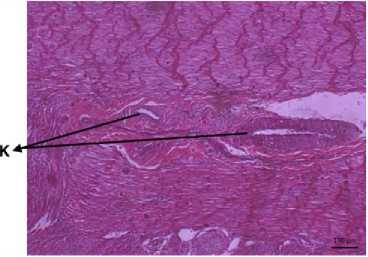

Picture 5. Tunica Muscoularis (HE) (200X), K: Blood vessel

Picture 6. Tunica Muscoularis (HE) (200X) L: Muscularis sirculair, M: Muscularis Longitudinal, N: Nerve.

Sel-sel yang ditemukan dalam lamina propria adalah sel goblet, crypt lieberkuhn, sama halnya yang dilaporkan oleh William et al. (2012). Sel goblet atau biasanya disebut sel mangkok letaknya tersebar diantara sel penyerap dan melekat pada juxta-luminal junctional complex, daerah kutub basalnya menyempit dan mengndung inti dan sitoplasma bersifat basofil (Suwiti, 2012). Lamina muskularis adalah lapisan otot polos yang memisahkan tunika mukosa dengan tunika submukosa (Althnaian et al., 2013). Pada lapisan tunika submukosa ditemukan kelenjar brunner dan unit sekresi. Pada lapisan tunika muskularis terdapat 2 lapisan muskularis longitudinal dan sirkular, kemudian terdapat pembuluh darah dan saraf, lapisan tunika muskularis yang berisi jaringan otot polos. Otot akan berkontraksi jika adanya chyme dan mendorongnya, hal ini diperkuat dari laporan William et al. (2012). Serosa adalah lapisan terluar dari duodenum yang berfungsi sebagai kulit luar usus. Membran serosa yang terbuat dari epitel skuamosa sederhana memberikan permukaan licin dan mulus untuk mencegah friksi antara duodenum dan organ di sekitarnya. Serosa juga mengeluarkan cairan serosa untuk